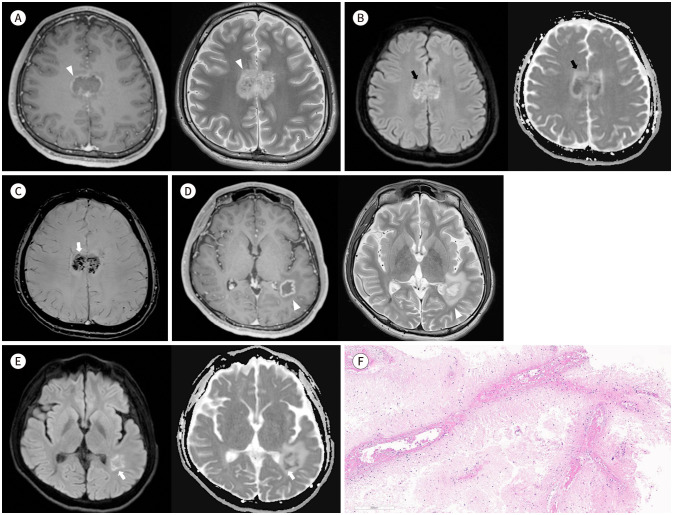

原发性中枢神经系统血管炎(PACNS)是一种罕见的中枢神经系统血管炎。在此,我们报告了一例难以与脑脓肿相鉴别的坏死型中枢神经系统血管炎的诊断和治疗。一名 19 岁的男性因视力模糊和头痛就诊。脑部核磁共振成像显示不规则边缘强化坏死肿块,胼胝体中央弥散高信号强度,左侧顶颞叶脑室周围弥散高信号强度。感度加权成像显示病变部位有多处点状出血。患者被诊断为异常脓肿或肿瘤性 PACNS。因此,我们最初用抗生素治疗患者,以排除脑脓肿的可能。然而,经过抗生素治疗后,脑部病变在磁共振成像随访中并无改善。我们对患者进行了手术活检,组织病理学诊断为坏死型 PACNS。经大剂量皮质类固醇治疗后,随访的磁共振成像显示坏死病灶变小。

Primary angiitis of the central nervous system (PACNS) is a rare vasculitis in the central nervous system. Herein, we report a case of diagnosis and treatment of necrotic pattern PACNS, which was difficult to differentiate from a brain abscess. A 19-year-old male presented with blurred vision and a headache. Brain MRI revealed irregular rim-enhancing necrotic masses with central diffusion-high signal intensity in the corpus callosum and peripheral diffusion-high signal intensity in the left parietotemporal periventricular area. Susceptibility-weighted imaging revealed multiple punctate hemorrhages in the lesions. The patient was diagnosed with unusual abscess or tumefactive PACNS. Therefore, we initially treated the patient with antibiotics to rule out brain abscess. However, the brain lesions did not improve on follow-up MRI after the antibiotic treatment. Surgical biopsy was performed, and the histopathological diagnosis was PACNS with a necrotic pattern. The necrotic lesions became smaller on follow-up MRI after high-dose corticosteroid treatment.